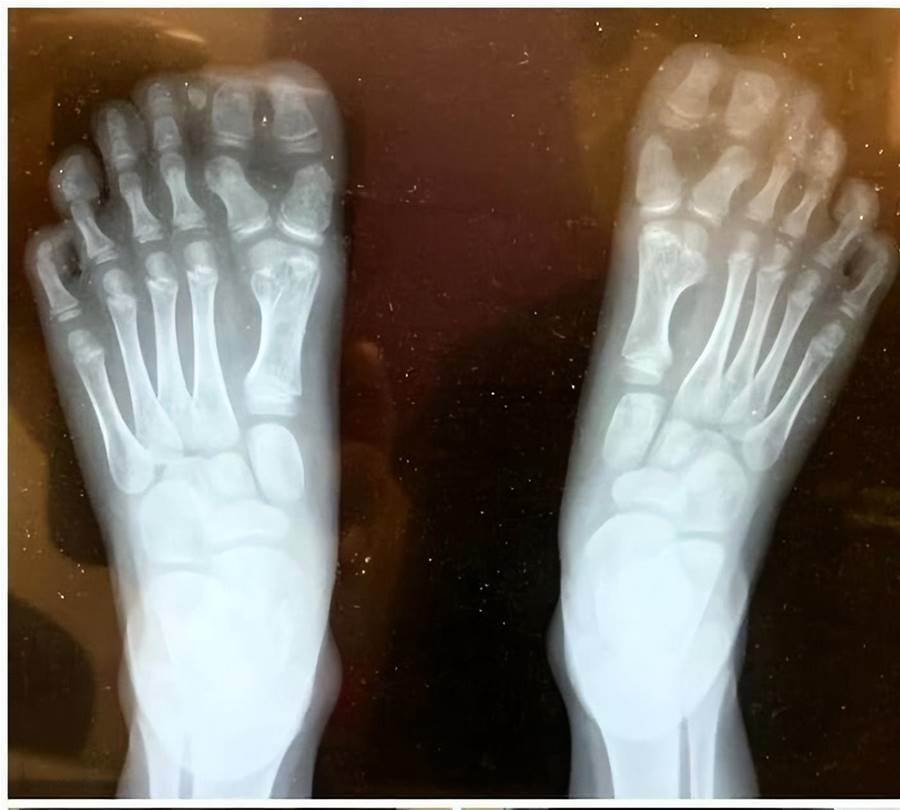

我兒子每只腳上有兩個大腳趾